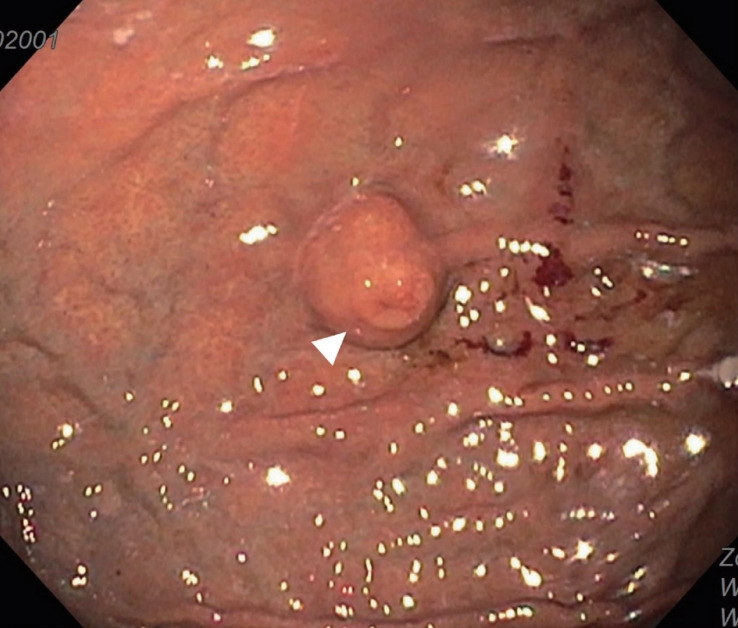

A Subepithelial Lesion of the Stomach Observed During Screening Endoscopy.

胃镜检查时发现胃上皮下病变。